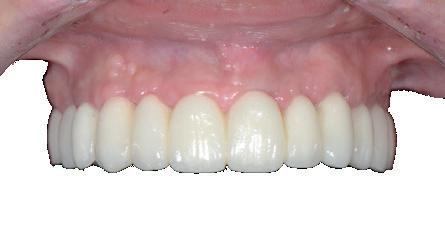

Situation avant la prise d’empreinte en sept. 2009

Situation pré-opératoire 09/2018 09/2018

Contrôle à 10 ans en septembre 2018.